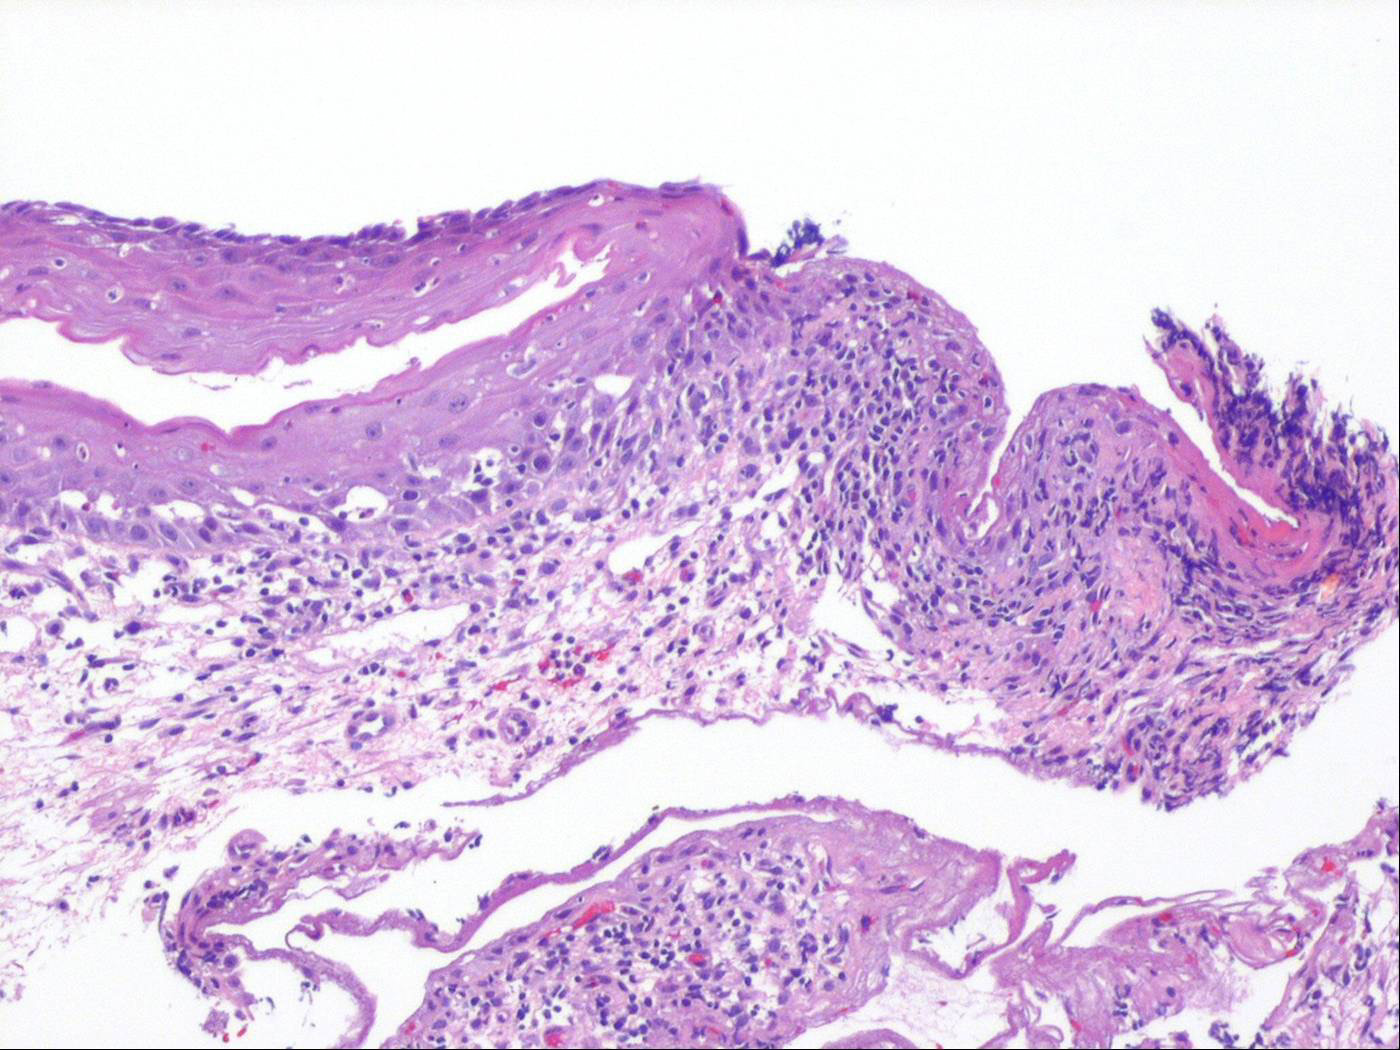

Oropharyngeal lichen planus = الحزاز المنبسط الفموي البلعومي